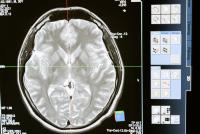

Premieră mondială: Un vierme viu, de 8 cm, a fost găsit în creierul unei femei